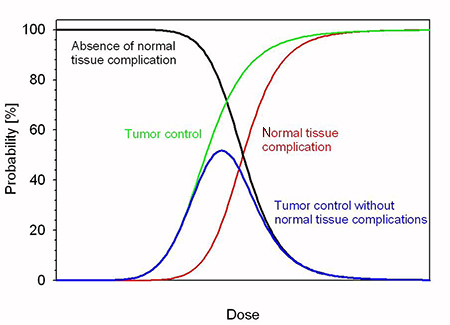

5.2.1. Motivation to use and expand x-rays and particle therapy

The use of x-rays in radiotherapy (RT) is now the most common method of RT for cancer treatment. While x-ray therapy is a mature technology there is room for improvement. The current challenges are related to the accurate delivery of x-rays to tumours involving sophisticated techniques to combine imaging and therapy. In particular, the ability to achieve better definition and efficiency in 4D reconstruction (3D over time) distinguishing volumes of functional biological significance. Further technical improvements to reduce the risk of a treatment differs from the prescription and moving towards 'personalised treatment planing' are being made. Some of these techniques such as: image-guided radiation therapy (IGRT), control of the dose administered to the patient (in vivo dosimetry) or adaptive RT to take into account the morphology changes in the patient, are the state of the art and are being implemented in the routine operation of these types of facilities. An example is the so-called MR linac, which provides magnetic resonance (MR) and RT treatment at the same time. Finally, the reduction of the accelerator costs and the increase of reliability/availability in challenging environments are also important research challenges to expand this kind of RT in low- and middle-income countries (LMICs).

Proton and ion beam therapy has growing potential in dealing with difficult-to-treat tumours, for example, because of the risk of damaging neighbouring sensitive tissues such as the brainstem or visual nerves in the case of head tumour treatments. Also, some treatments may benefit from the use of particles that deliver doses with greater radiobiological effectiveness (RBE) and higher local precision, notably carbon, and in the near future also helium ions.

Recent investigations using ultra-short and ultra-high dose rates (called FLASH) of electron beams showed growth retardation of tumours with the same effect as in conventional therapy, but with minimized impact to the surrounding tissue. FLASH with proton and ion beams is expected to offer additional healthy tissue sparing from beam stopping in the tumour—but the research on this topic is still not completed, and the experiments and evaluations are ongoing. Healthy tissue sparing with FLASH would enable a dose increase as well as a significant reduction of treatment time without additional aggravations. These new key findings may influence the accelerator development for particle therapy considerably in the next future.